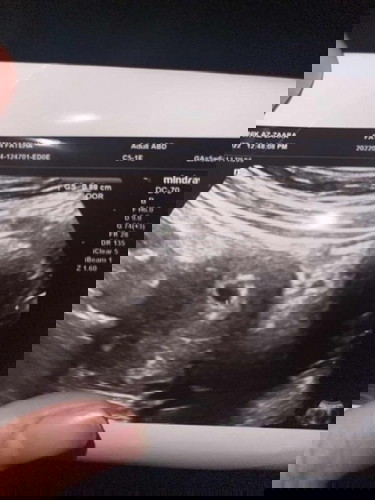

Selamat petang semua. Saya nak tanya, saya last period 1Feb. Skrg sy scan pregnant cume xleh detect lagi berapa minggu sebab cuma ada kantung kecil. Xde janin lagi. Saya scan pagi. Doc cakap kantung elok bulat, kat atas tak ada tanda2x gugur. Lepas tu sy jalan2x mall, balik tu nk solat maghrib, ade darah. Agak banyak. N ada ketulan kecil 2. Bila picit, xhancur. Kecik sgt. Tp skrg ni dh 10’malam, xada ketulan dah. Kenape ye? Sbb baru pagi sy scan semua dlm keadaan baik. Boleh jadi molar pregnancy ke kalau kantung elok bulat? Atau ade sesiapa pernah alami? #pleasehelp #ingintahu